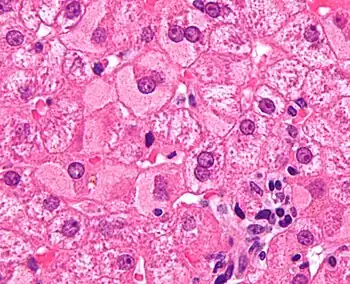

Ground glass hepatocytes

Ground glass hepatocytes Primary biliary cirrhosis